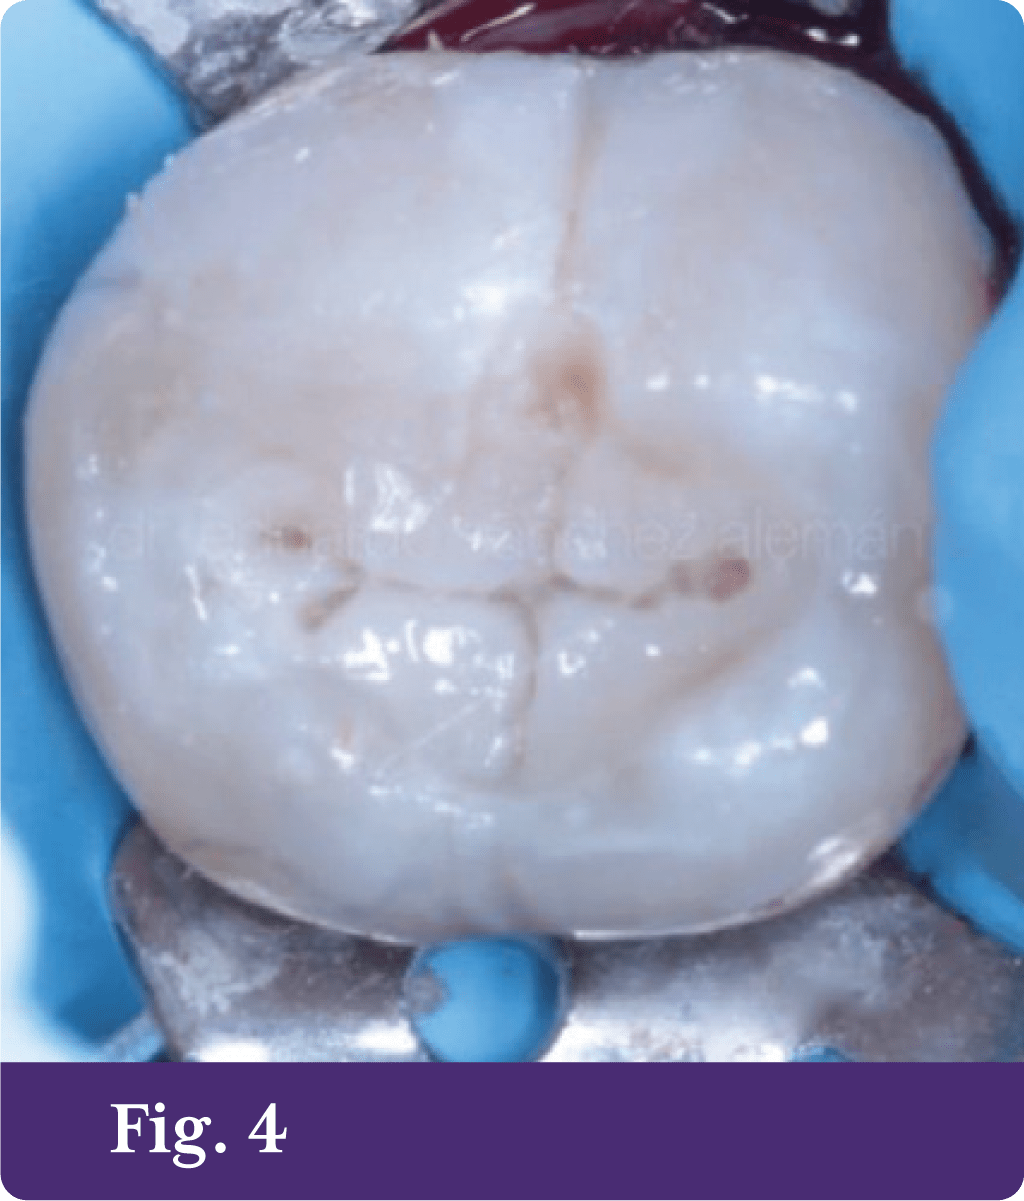

Se presenta paciente de sexo masculino de 55 años de edad a la consulta dental porque presenta dolor a los estímulos frío-calor en el segmento posteroinferior izquierdo, señalando con su dedo a los molares 36 y 37. Se diagnostica hiperemia pulpar reversible, ya que los síntomas tienen duración de menos de un minuto y son provocados por los diferentes estímulos antes mencionados. El paciente refiere que las obturaciones fueron realizadas aproximadamente hace 20 años. A la exploración clínica se detecta en el órgano dentario 37 una obturación con amalgama en la cara oclusal y dos obturaciones en la cara vestibular, en superficies anatómicas y todas presentan zonas de pérdida de sellado marginal (fig. 1 y 1A).

En el piso de la cavidad oclusal se observa dentina reaccional en tono marrón oscuro; en general, las cavidades se ven con buen soporte estructural y prácticamente no se modifican. Se realiza alisado de paredes, desinfección con clorhexidina durante 15 segundos, se acondiciona el tejido adamantino con ácido ortofosfórico al 34% durante 15 segundos, después se lava y retira el exceso de humedad, también se utilizó adhesivo Self etch de dos pasos, dos frascos (primer y bond) de acuerdo a las indicaciones del fabricante y se procede a las obturaciones de las cavidades con composite Aura SDI (fig. 3)3,4 siguiendo las instrucciones. Finalmente, la técnica de obturación fue estratificación oblicua,5, 6 los estratos de dentina fueron hechos con composite color D3,6 (fig. 4).